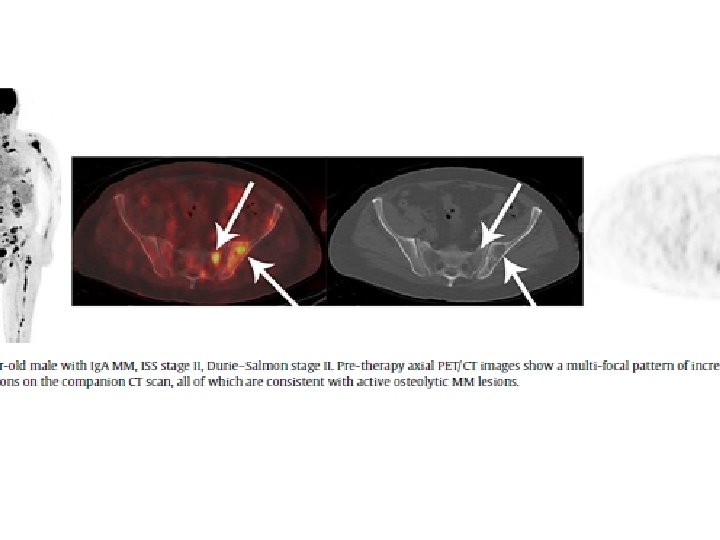

2014 * 18 F-FDG • Increased uptake on PET is not adequate for diagnosis M. M. Underlying osteolytic bone desctruction is needed. • Recommended in smouldering M. M and solitary plasmocytoma “Each focal lesion must be 5 mm or more in size”

Criterios de respuesta a la terapia: Recomendaciones Validado en ensayos clínicos: “French criteria” Lesión focal Positiva: Pre-tratamiento FDG > captación fisiológica de MO “columna y pelvis” y/o > captación hepática con o sin correspondencia en CT Negativa: Post-terapia Lesión lítica estable en CT, nueva lesión osteolítica o captación focal FDG > hígado Captación asociada a lesión lítica por CT que muestra halo escleroso captante Equivocal: Captación en Fx costales o en otras FX óseas con cambios esclerosos por CT Infiltración M. O Positiva: Captación esquel axial/apendicular > hígado Negativa: Captación esquel axial/apendicular ≤ hígado Captación heterogénea > hígado Mesguich C. et al, Eur J Radiol 2014; 83: 2203 -2223 (Mount Sinai, NY)

Treatment response assessment • Lytic lesions XR and CT → sclerotic rim after treatment Baseline PET Residual tissue XR-CT Size Not differentiate from active disease • • PET Metabolic activity Differentiate from tumor viability PET/TC could be useful in the assessment of treatment response: – Extramedullary disease – After chemo, after induccióntreatment, before and after SCT – Metabolic Response: CMR; PMR; Non-MR, PMD PET not indicated/validated to evaluate treatment response in MM – Uniform response criteria from IMWG: • Disappearance of any soft tissue plasmacytoma • > 50% reduction in size of soft tissue plasmacytoma PET after treatment